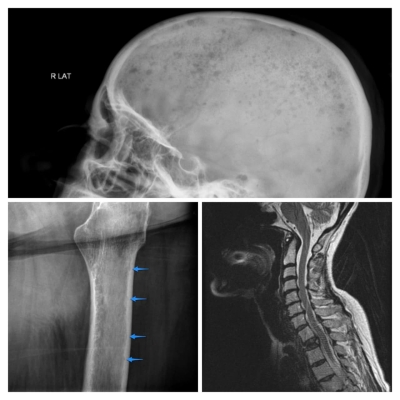

Radiograficamente falando, inicialmente podem nem haver nenhum sinal da doença — “apesar da presença de sintomas“. Mas quando aparece, tem predileção pelas “vértebras, costelas, crânio, cintura escapular, pélve, ossos longos” e até nas “estruturas extraesqueléticas (mieloma extraósseo” — mas este último é bem raro). Nestas regiões o mieloma múltiplo se manifesta na forma de “2 principais padrões difusos”:

Vejam exemplos de “crânio em gota de chuva”, “escala endosteal” e vértebra plana nas imagens abaixo:

Sim, é bom que estejamos atentos. Porque um paciente que apresente dores lombares e esteja com estes sinais radiológicos é um prato cheio para para ocorrer uma fratura patológica por ajustamento. E como profissão a gente já tem dor de cabeça suficiente.